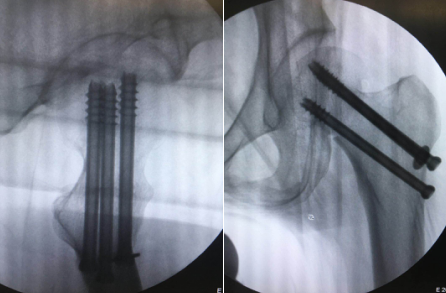

术中,先将患者置于牵引床上闭合复位,C型臂透视见骨折端对位良好;接着,机器人“C臂”透视对患者股骨颈部位行三维扫描,图像被同步传输至骨科手术机器人系统。同时,在导航系统屏幕上规划好钉道。随后,机器人的机械臂将手术工具精确定位到手术位置,套筒指向目的钉道的进钉点。手术小组沿着套筒钻入导引针,确认位置无误,再把空心加压螺钉通过导引针固定,拔出导针。

手术历时50分钟,顺利完成。任海东主任说,以往股骨颈骨折如何精准置钉一直是个难题,但在机器人导航辅助下,手术团队将精确度误差控制在0.2毫米以内。整个手术过程中,透视次数大幅减少,对患者及医护人员的放射保护大大增强。患者术后几乎感觉不到疼痛,换药时看到自己的伤口仅为1厘米时,不禁惊叹:“伤口这么小!真没想到!”